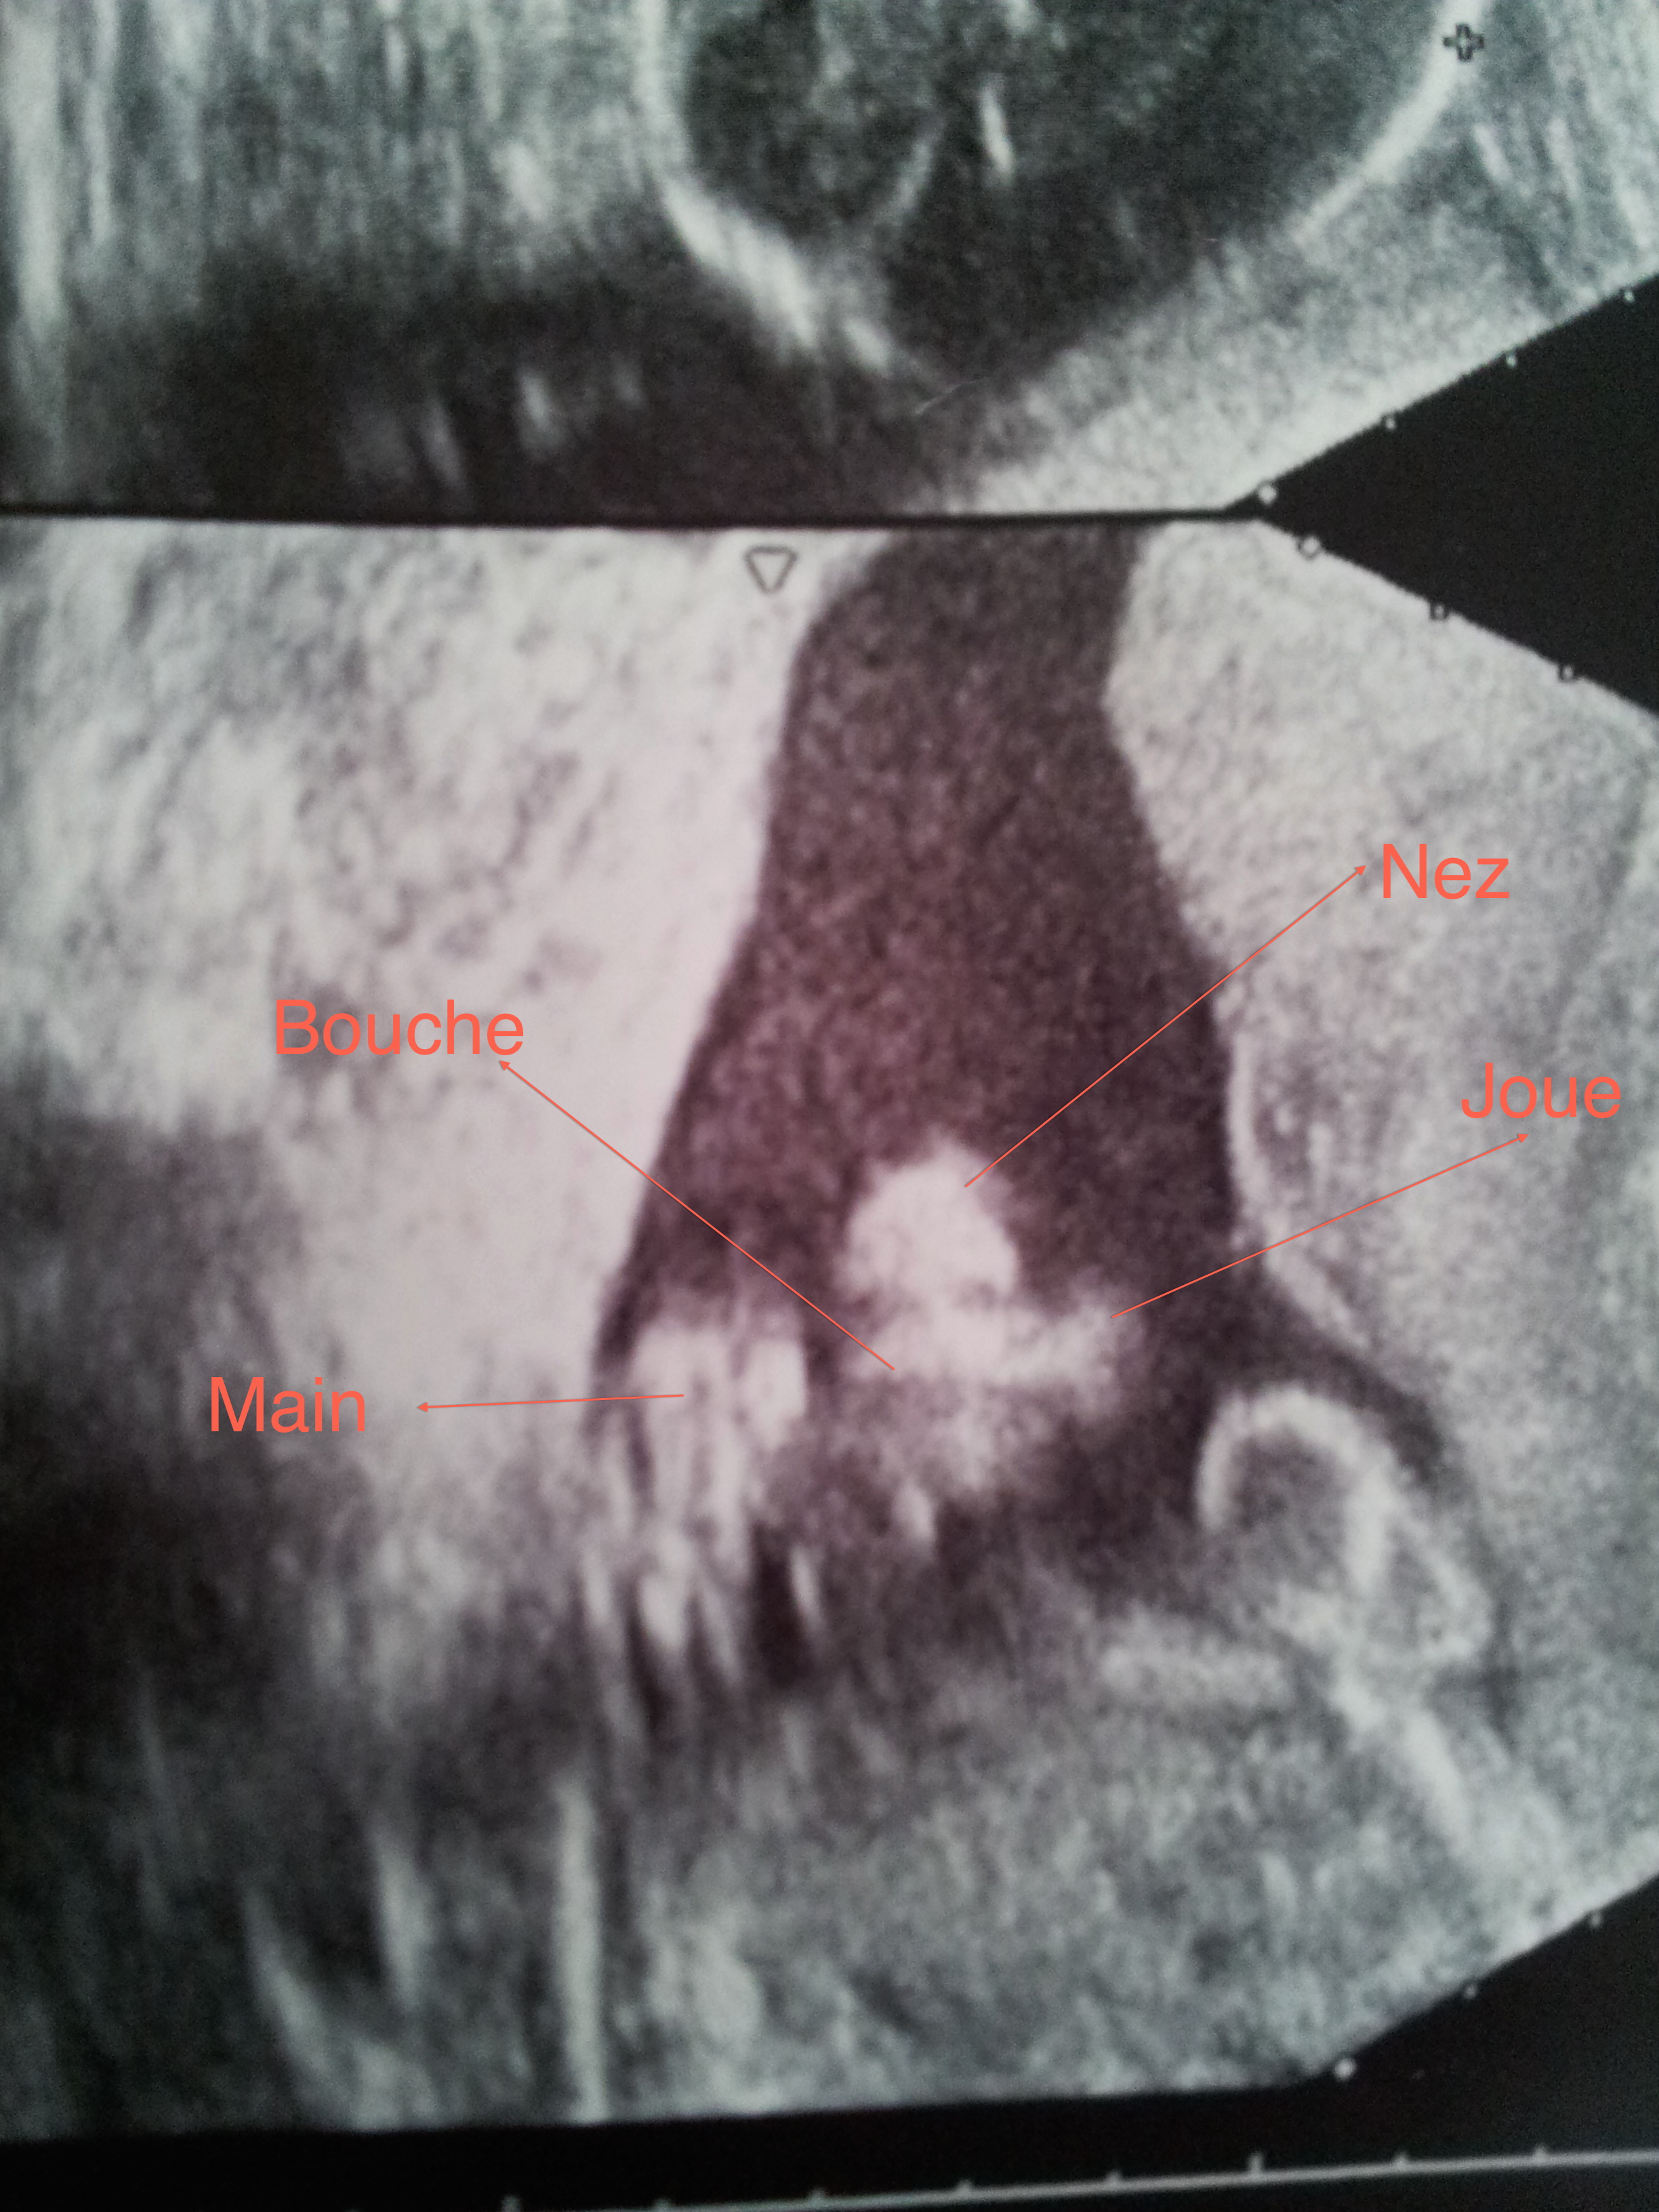

Peut être parce qu’au fond j’ai apprécié quand même un peu attendre chacun de mes enfants. Certes, ça n’a pas été une partie de plaisir et je m’en souviens encore très bien mais, ça reste un moment à part. Et puis surtout, jamais je ne revivrai ça (et vous pouvez très bien dire « ne jamais dire jamais », perso c’est catégorique !), les barres sur la bandelette, le secret des premières semaines, le ventre qui s’arrondit doucement, la première, deuxième, troisième échographie, l’annonce du sexe de bébé, les premiers coups, l’attente sans savoir quel jour bébé aura décidé de venir nous rencontrer, les premières contractions (oui pas les dernières hein, c’est encore frais dans ma mémoire ça…), la rencontre…

J’ai eu la chance de vivre 2 grossesses, peu importe comment je m’en souviens ou comment je les ai vécues au fond. Elles sont ce qui a permis à mes filles d’être parmi nous en bonne santé aujourd’hui. Un petit miracle qui m’émerveille toujours, comment passer d’une tête d’épingle à ce joli bébé qu’on vous pose sur le ventre en 9 mois…